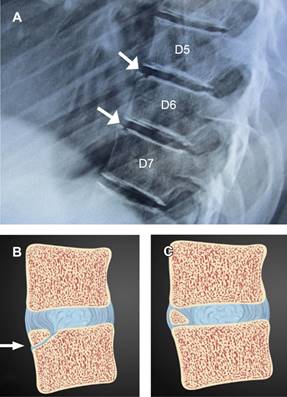

Figura 1: Radiografía lateral de espina dorsal y lumbar, mostrando cifosis dorsal e hiperlordosis lumbar de tipo postural, como hallazgo se observan C6 y C7 catalogadas como vértebras limbus (flechas).

Figura 2: A) Radiografía lateral de columna lumbar mostrando a las vértebras C6 y C7 con defecto triangular en borde superior, correspondiendo a hueso limbus (flechas). B) Esquema demostrativo de herniación intraósea del núcleo pulposo a través del anillo apofisario vertebral (flecha). C) Esquema que muestra un hueso intercalar como diagnóstico diferencial.